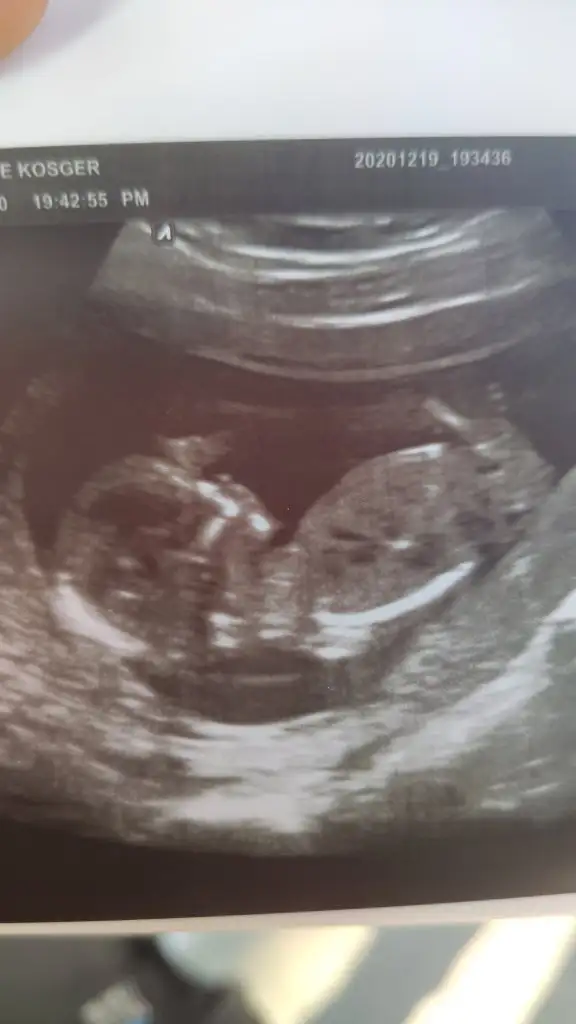

Karından bakılmıştı ilk doktora gidişim kalp atışlarını duyduğumuz zamanKarından USG ise erkek vajinalsa kiz @sip_sevdi

Bakalım sonuç nolcakKarından bakılmıştı ilk doktora gidişim kalp atışlarını duyduğumuz zaman

Evet yolk sac nerede oluştu ise bebekte orada olusur ilerki haftalarda bebek yer değiştirir buna göre karından bakıldı ise kız vajinal ise erkekEvet ilk bebekhayırlısı sağlıklı olsunda kiz erkek farketmez tabi

Önceki solda görünüyordu burda sağda görünüyor ve yolk sac önemli çünkü bebek ilk orada oluşuyor ve buna göre yani sağda görünüyor karında ise kız vajinal ise erkekAa ama burda tam tersi demiştiniz

Çünkü bebek orada görünüyor o nedenle karından ise erkek vajinal ise kız sizde karından dediniz ve erkekti ama ilk yolk sac paylasmis olsaydınız ilk kız derdimAa ama burda tam tersi demiştiniz

Cnm banada bakarmisin 12+3 karından ultrasonla cekildi ama ters çıktıEvet yolk sac nerede oluştu ise bebekte orada olusur ilerki haftalarda bebek yer değiştirir buna göre karından bakıldı ise kız vajinal ise erkek